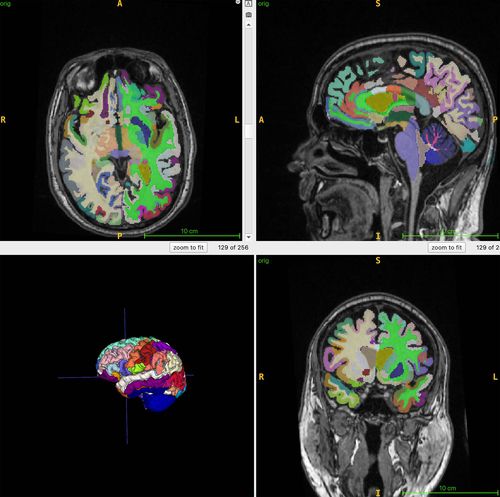

뇌 나이 추정을 위한 뇌 MRI 영상 |

연구팀은 이 연구에서 뇌의 구조적 MRI 영상의 부위별 부피를 기반으로 추정한 뇌 나이와 전신 MRI로 측정한 총근육량과 내장지방, 피하지방 사이의 연관성을 인공지능 알고리즘으로 분석했다.

이들은 4개 지역 거주자 1천164명(평균 나이 55.17세)을 대상으로 전신 MRI를 촬영하고 이를 지방과 체액, 근육 등이 다른 색으로 보이게 하는 기법과 결합해 총근육량과 내장지방 피하지방, 뇌 나이를 정량화했다.